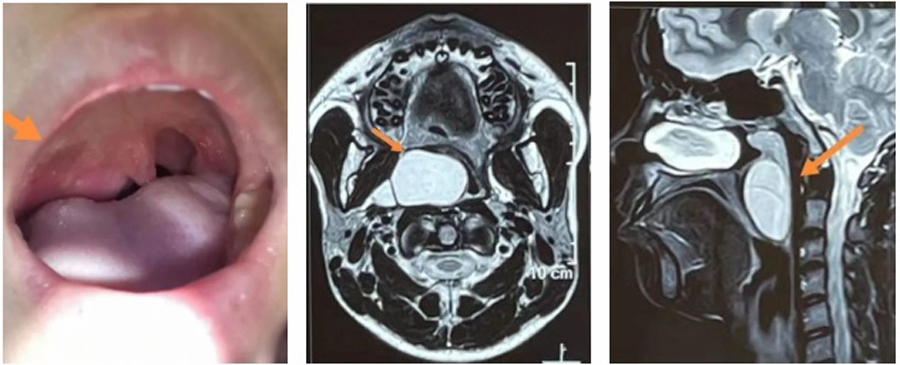

小君因为咽部异物感,右侧面部膨隆来蜜桃视频 就诊,平日并没有咽痛、吞咽困难、消瘦等。在检查中,医生发现,小君右侧软腭明显凸出,边缘可见肿物向内下方膨隆、悬雍垂(小舌头)整体左移、腭弓向内下方偏移,鼻咽镜检查发现肿物上极已达鼻咽部后鼻孔层面,下极到喉部会厌缘平面,跨度大,基地宽。根据小君临床表现,估计肿物生长已数年之久,为明确肿物性质,医生立即进行了进一步检查。通过增强CT、核磁检查明确了肿物的边界,上边界达鼻咽顶、下边界在声门上,外边界与颈外侧动静脉相毗邻、内边界将咽部内侧壁完全向内下方挤压。影像显示肿物边界清晰,结合其临床表现,考虑恶性可能性不大,但由于肿物巨大,向内侧已到中线位置,向外侧,小君的右侧面部已出现略向外膨隆状态,手术迫在眉睫。

确定手术治疗后,张薇副院长和团队根据检查情况,积极制定手术方案。手术最大的风险在于肿物的位置特殊,与颈内动静脉关系紧密,稍有不慎损伤,后果不堪设想。手术入路是经内镜从口咽进入?还是经颈外侧切口进入?张薇副院长仔细分析了手术方案:如果从咽部进入,可以避免皮肤切口造成的颈部瘢痕,但对术者的手术能力要求很高,需要内镜辅助,尽量清除囊壁的同时要注意保护好血管;如果从颈外侧进入,切口较大,造成颈部瘢痕,可能影响患儿颈部美观,甚至影响升学,且手术需跨越整个动静脉区,才能到达肿物的位置,并且有形成咽瘘、神经血管损伤等并发症。为避免颈部巨大瘢痕对患儿的影响,儿医团队还是决定经口咽入路,迎接挑战,尽最大努力,保患儿安康。